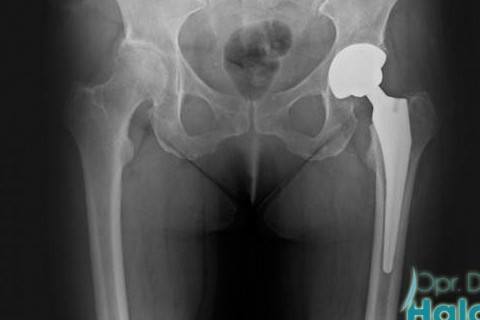

Kalça Protezi

Kalça Protezi Nedir?

Kalça eklemi insan vücudunda en büyük eklemdir. Bununla birlikte vücut ağırlığının büyük bir kısmını taşıması ve gün içerisinde sürekli aktif olması nedeni ile zaman içerisinde aşınmakta ve yaşlanmaktadır. Gerek kireçlenme problemleri, gerekse kırılma ya da avaskuler nevroz problemleri kalça eklemindeki kemik ve kıkırdak dokunun aşınması ve zayıflaması sonucunda gelişmektedir.

Kalça kireçlenmesi, kalça kırıkları ve avaskuler nevroz nedeniyle kalça protezi yapılır. Kalçadaki kireçlenme ilerlediyse, hayat kalitenizi düşürdüyse total kalça protezi zamanı gelmiş demektir. Ameliyat kararını doktor değil hasta verir.

Kalça protezi son yıllarda çokça başvurulan bir ortopedik tedavi yöntemdir. Farklı materyallerden birleşiminden tasarlanan kalça protezleri, insan dokusu ile tam uyumlu olmaktadır ve herhangi bir alerjik reaksiyona neden olmamaktadır.

Kalça Protezi Çeşitleri

Kalça protezlerini iki gruba ayırabiliriz. Total protez tarzını genelde diz protezinden tanıyoruz. Bu protez, bu alanda en sık kullanılan protez yöntemidir. Bu teknikte kalça kemiği kadar yuva da değişir. Bir tek kalça kemiğinin onarılması ise parsiyel teknik olarak adlandırılıyor. Ortopedik cerrah, hastanın özel durumunda bağlı olarak bu iki teknikten hangisine karar vermesi gerektiğini analiz edecektir.

Total Kalça Protezi

Total kalça protezi ameliyatı açık yöntem ile uygulanmaktadır. Cerrahın tercihine bağlı olarak uygun konumda kesi açılmaktadır. Ameliyat süresi yaklaşık 2 ila 2,5 saattir. Hasta ameliyat sonrasında ilk 3 gün hastanede yatırılmaktadır.